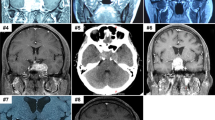

A 4-month-old boy presented with a progressive macrocephaly for which magnetic resonance imaging (MRI) of the skull was performed and revealed a mass located on the cerebellar falx (Figure 1a). Histopathological analysis of biopsy material showed a poorly differentiated monomorphous tumor (Figure 1c) made of round-shaped tumor cells with scant cytoplasm and loss of nuclear immunoreactivity for INI1 antibody (Figure 1d). Therefore, a diagnosis of AT/RT, WHO grade IV, was made.1 An abdominal computed tomography scan evidenced a lesion within the left kidney suggestive of a RT (Figure 1b) in a context of RPS. The patient died 6 months after the initial diagnosis.

Radiological and histopathological findings of patient 1 (a–d) and 2 (e–h) tumors: sagittal FLAIR magnetic resonance imaging showing hydrocephalus caused by a large hyperintense falx cerebellar lesion compressing the aqueduct of Sylvius (a). Computerized tomodensitometry scan displaying a well-circumscribed heterogeneous lesion of the right kidney on T1 sequence after injection of gadolinium (arrow) (b), composed of small and poorly differentiated cells (c; HE, × 380 magnification); loss of nuclear INI1 expression specifically observed in the tumor cells with preserved immunostaining in normal endothelial cells (d; × 380 magnification); axial magnetic resonance imaging showed an enhancing large hyperintense cerebellar lesion (e) and a second lesion within the left foramen of Monro on T1 sequence after injection of gadolinium (f); composed of poorly differentiated cells with typical features of rhabdoid cells in a part of them (g; HE, × 380 magnification); loss of the nuclear INI1 expression in the tumor cells (h; × 380 magnification).

Another boy of 8-month-old of age was referred in emergency owing to vomiting and progressive enlargement of the head. MRI displayed two voluminous contrast enhancing solid and cystic tumor masses, the first being protruding into the fourth ventricle (Figure 1e) and the second located in the left foramen of Monro (Figure 1f). A subtotal resection of the cerebellar tumor was performed. Microscopic examination displayed a poorly differentiated tumor proliferation, containing small rounded cells with large eosinophilic cytoplasms and nuclear loss of INI1 expression on immunohistochemical analysis (Figures 1g and h), that led to the diagnosis of AT/RT, WHO grade IV.1 The patient was started on chemotherapy (vincristine and doxorubicin). One month later, MRI revealed progression of the supratentorial tumor. The patient died 13 months after the initial diagnosis.